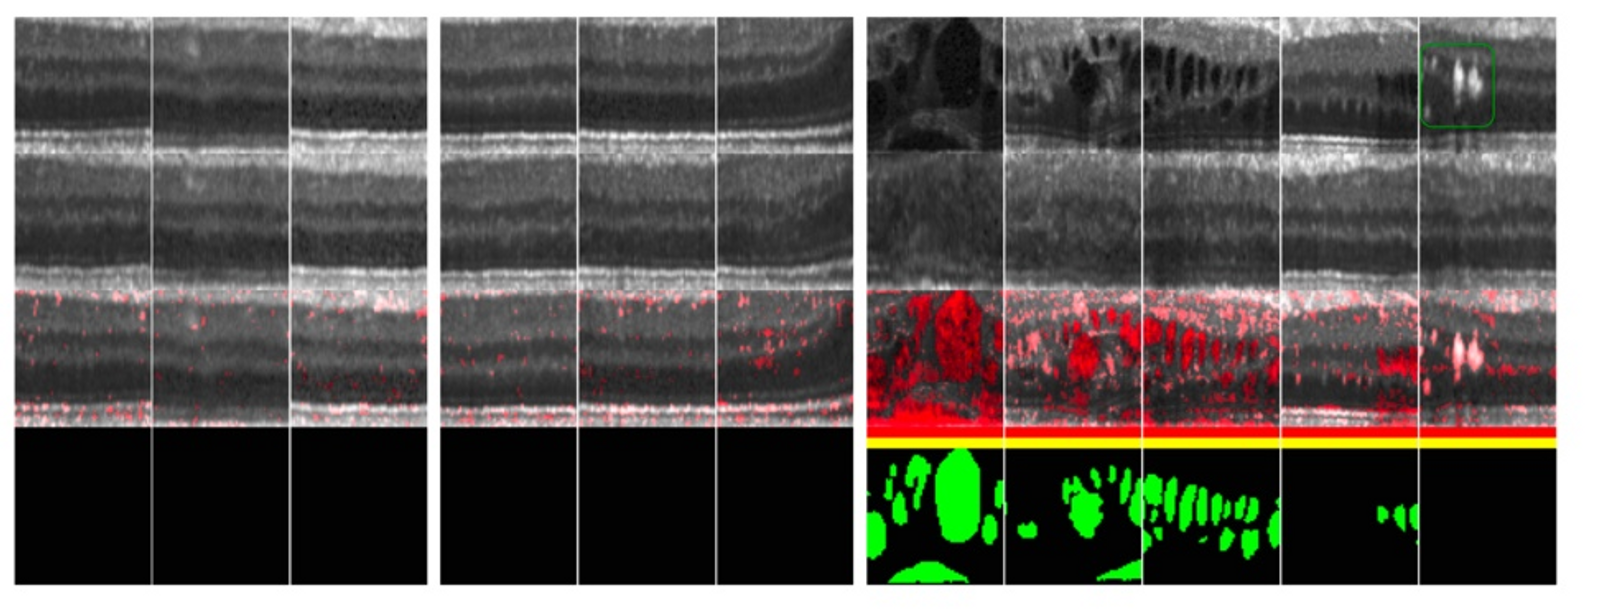

실험은 10000장의 grey scale로 구성된 64*64 사이즈의 망막 데이터로 학습을 진행하였고, test data는 같은 조건을 8192장을 사용하였다. normal과 abnormal이 각 몇 장으로 구성되어 있는지는 안 나와있다.

쨌든 model은 DC GAN을 약간 변형시켜 각 convolution의 channel을 절반씩 줄인 것을 사용하였고, 행의 정보는 다음과 같다.

1행: 진짜 이미지

2행: G가 생성한 가짜 이미지

3행: residual 이미지

4행: 인간이 라벨링 한 비정상 영역

결과적으로 보면 해당 모델이 비정상 영역을 잘 포착한 모습을 볼 수 있다.